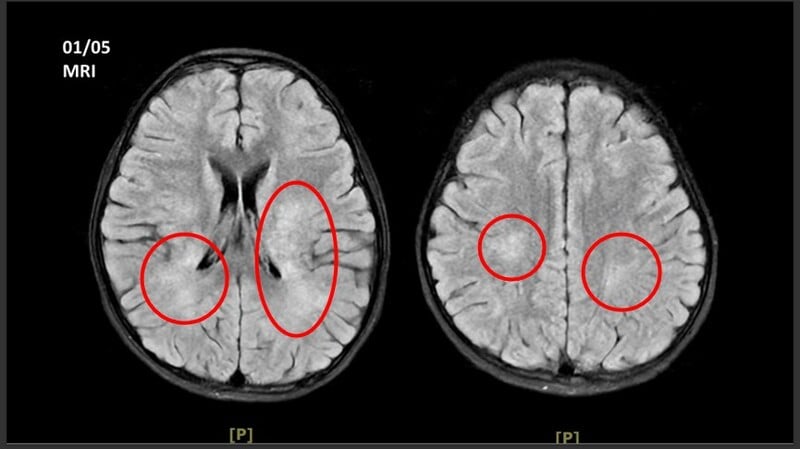

王傳育主任指出,女童當時血壓明顯偏高,心跳也較慢,醫療團隊擔心已有腦壓升高或顱內病變,立即安排住院,並同步給予降低腦壓治療與核磁共振掃描。檢查結果顯示,小腦、視丘及大腦白質、皮質下都可見異常訊號,符合急性散播性腦脊髓炎的影像表現。

醫療團隊進一步將血液送往台大醫院檢驗自體免疫抗體,最後證實為MOG抗體陽性相關疾病。王傳育主任說明,MOGAD是一種自體免疫性脫髓鞘疾病,當異常抗體攻擊腦部、視神經或脊髓外層的髓鞘時,就可能造成神經發炎與功能異常。九歲以下兒童較常以ADEM形式表現,較大的孩子或成人則可能出現視神經炎、脊髓炎,甚至肢體麻痺等較嚴重症狀。